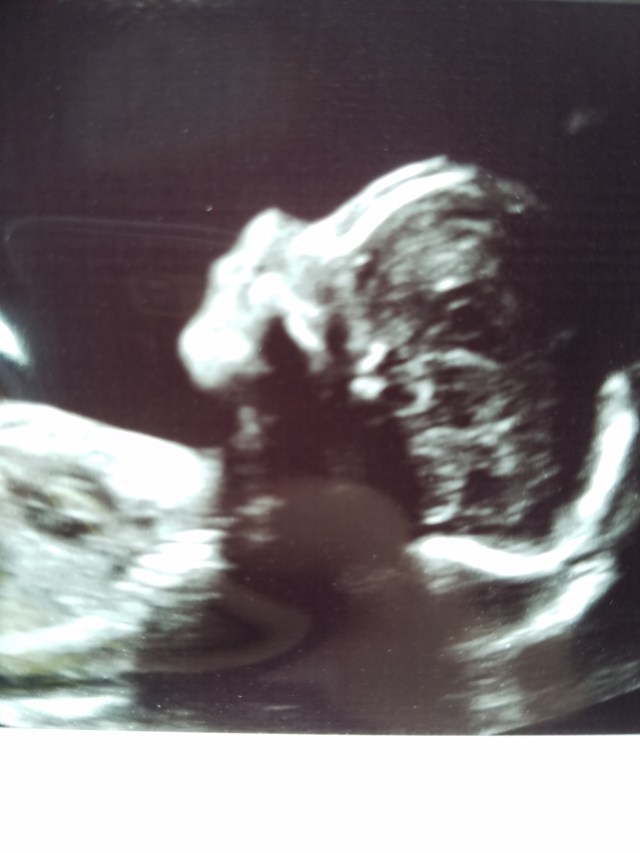

22 Weeks!